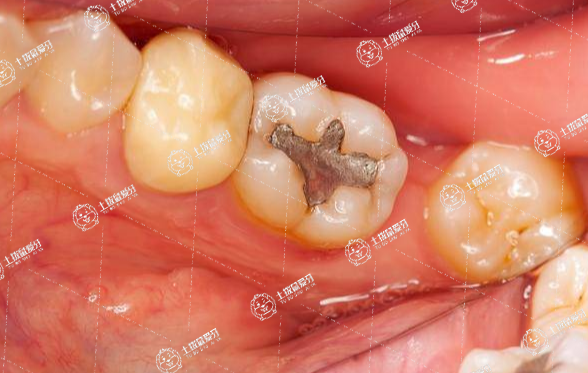

我們常常人到中年后,在生活當(dāng)中總是容易出現(xiàn)各種牙齒問(wèn)題,其中,齲齒就是非常常見(jiàn)的一種牙齒壞掉類型,因此,不少人在牙齒壞掉后就想著及時(shí)拔掉壞掉的牙齒進(jìn)行牙齒修復(fù)拔牙之后必須種植牙嗎?一起來(lái)了解一下。

拔牙后不一定需要種牙,應(yīng)根據(jù)所拔牙齒類型和口腔情況來(lái)選擇,多數(shù)情況下拔牙后是需要種植修復(fù)的,但口腔有種牙禁忌證時(shí)不適合種牙;此外,如所拔牙齒是智齒,或由牙齒擁擠導(dǎo)致拔牙,通常也不需要種牙。

1.種牙是將替代天然牙根的種植體植入頜骨,以獲取類似于牙固位支持的修復(fù)體,多數(shù)情況下拔牙后是需要種植修復(fù)的。

一般拔牙后,拔牙創(chuàng)傷以后是需要鑲牙,種植牙是一種很好的消炎方法,也是現(xiàn)在目前市面上比較流行的鑲牙方式。因?yàn)榉N植牙是缺一顆牙齒種一顆牙就可以,不像傳統(tǒng)的修復(fù)方法固定修復(fù),如果缺了一顆牙還要磨出兩邊的好牙來(lái)恢復(fù)中間的缺失牙。